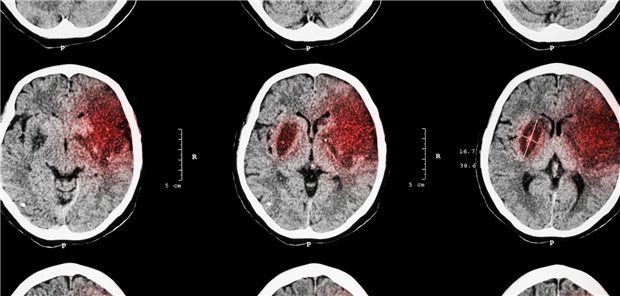

Schlaganfall: Das sind Grenzfälle der Thrombolyse

Ergebnisse der Studien ASSET-IT und MOST

Was nützt die Lyse-Augmentation bei Schlaganfall?